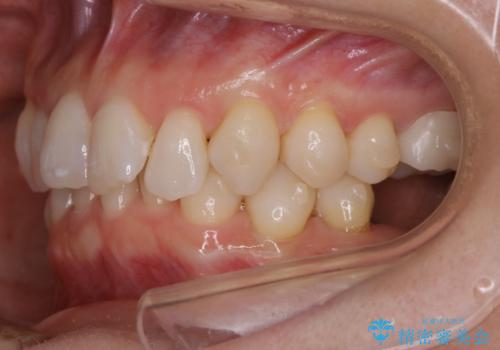

【抜歯】矯正治療とインプラントで正常な噛み合わせを実現

- 元々は矯正治療を主訴にご来院されました。

治療を始めるにあたり、精密検査を受けていただき全体の状況を把握したうえで矯正治療の計画を立てることとなりました。

その過程で左下の6番目の歯は治療が必要な状態であることが分かり、被せ物を外して内部を確認してみると根が破折してしまっていることが判明しました。

歯が深い位置で破折している場合は基本的には抜歯が選択されます。

様々な治療プランを患者さんと相談させて頂き、最終的にインプラントで噛み合わせを回復させていくこととなり、まず悪くなっている歯を抜歯することから開始しました。